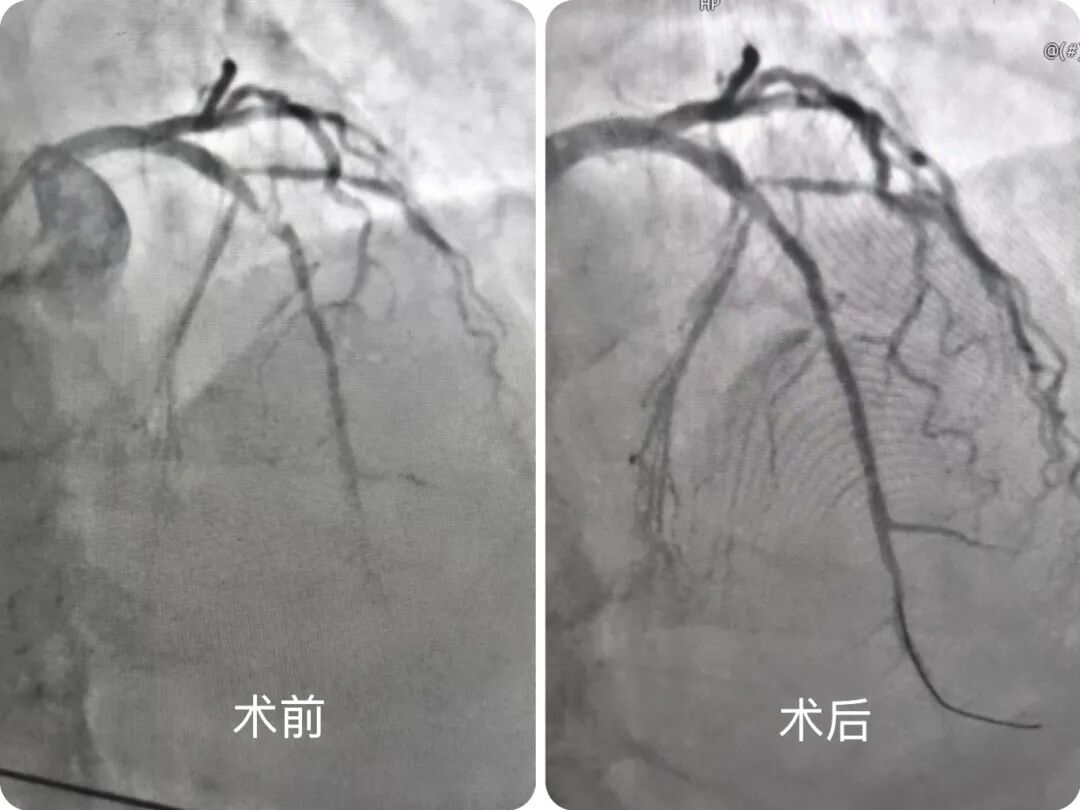

造影很快明确病因——前降支狭窄程度达99%,近段还嵌着血栓,急诊科主任郑晓晖、副主任医师马曹等专家精准操作,为患者实施“冠状动脉造影+前降支药物涂层球囊植入术”。随着药物球囊缓缓扩张,堵塞的血管被顺利打通,血流重新滋养心肌。

从患者入院(Door)到血管开通(Balloon),整个D to B时间仅用20分钟。目前,患者症状缓解,转入病房进行观察治疗。